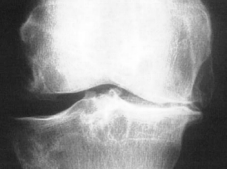

Bei der Arthrose (Bild rechts Kniegelenksarthrose) ist die mechanische Eigenschaft der Gelenkflüssigkeit

erheblich beeinträchtigt.

Diese kann dadurch die Pufferfunktion nicht

mehr erfüllen. Die mechanische Belastung des Gelenkes nimmt zu, der

Knorpel wird überlastet.

In weiterer Folge treten Schmerzen,

Entzündungen und Bewegungseinschränkungen auf.